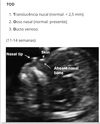

Aconselhamento genético O que o exame biofísico avalia?

Valor da translucência nucal ao USG que sugere síndrome de Down?

V ou F? Parâmetros avaliados ao USG de 1º trimestre são: transluscência nucal, doppler de artéria umbilical e cerebral média.

Falso. Parâmetros avaliados ao USG de 1º trimestre são: transluscência nucal, doppler de ducto venoso e osso nasal.